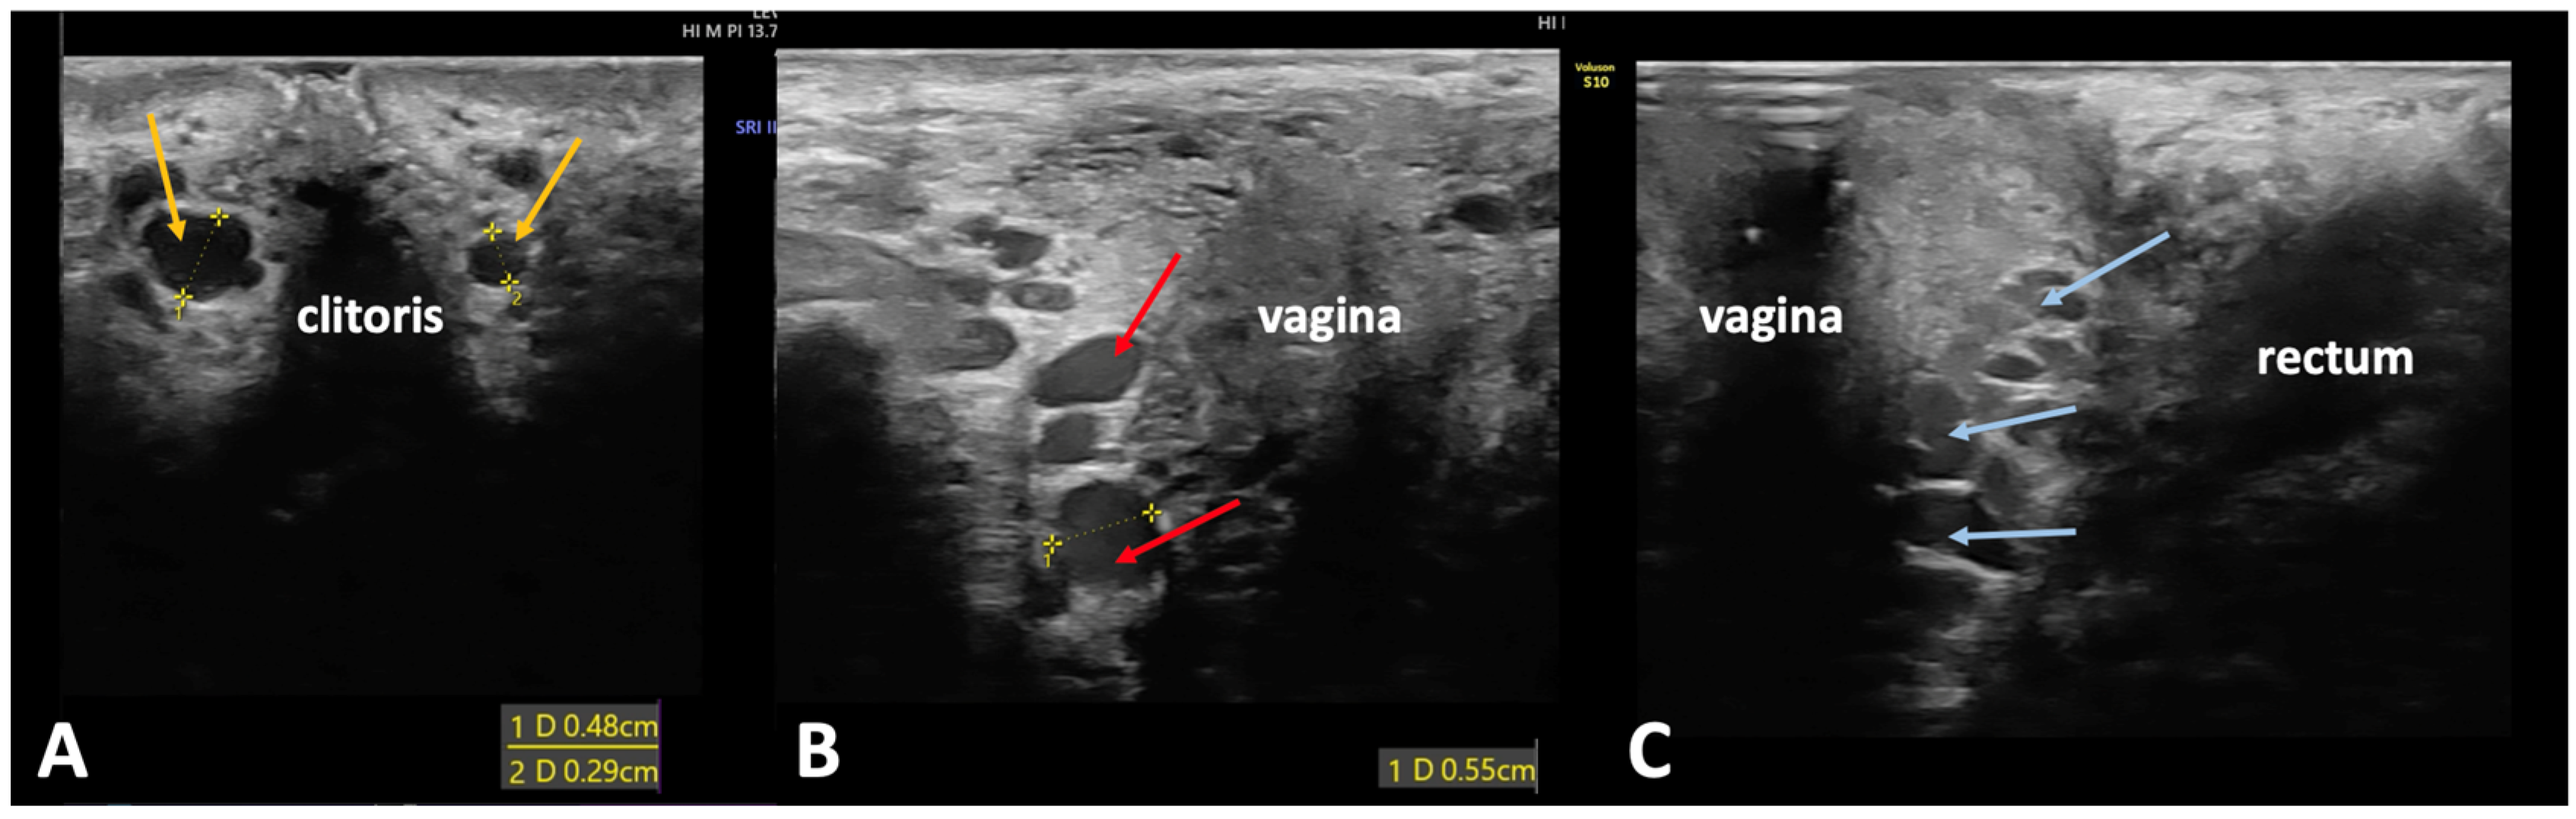

2.2.1. Transvaginal Ultrasonography